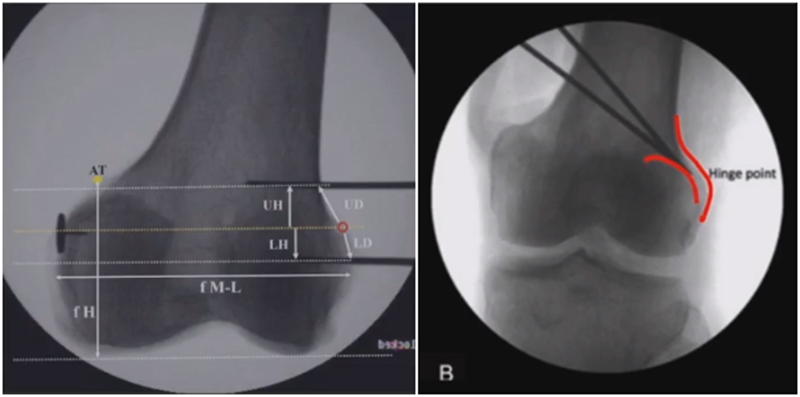

3、选择合页位置和截骨线

合页点的选择与HTO一样,通常需要尽可能接近畸形部位,既要有很好的骨质结构,还要有坚韧的软组织覆盖,以保证稳定性和术后有良好的血运。合页宽度不宜太长,通常保留在5mm。

合页点定位有两种方法,一种为定位在股骨外后髁上缘2mm位置,通常将此区域叫做“鹰嘴区”,以此为解剖标记法来定位合页点。

另一种通过导针从截骨入点向股骨外后髁后缘打出一条切线,此切线与外侧骨皮质的交点,也可作为合页点,这种方法称为导针法。这两种方法在手术之中是可以互为验证的。

合页点处于松质骨区,易形变区,如选择周边区域较脆易折断。另外合页点后方有小腿三头肌的附着点,有很好的的软组织和血运,综合来说作为合页非常合理。